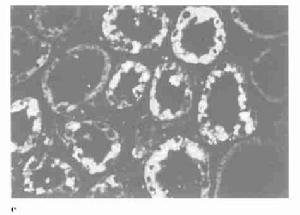

肺表面瀰漫性出血切面可見水腫和陳舊的出血。鏡檢見肺泡內出血,肺泡腔內常有吞噬含鐵血黃素的吞噬細胞局灶性肺泡纖維組織增殖。免疫螢光檢查顯示肺泡間隔和肺毛細血管基膜有免疫球蛋白和C3呈線狀沉積,腎臟病理改變似急進性腎小球腎炎此外,早期腎小球毛細血管呈局灶和節段性壞死,後期腎小球周圍有淋巴細胞浸潤為一特點。

肺出血-腎炎綜合徵4、腎活檢 除了常規光鏡檢查外,通常需要進行直接免疫螢光染色。免疫介導的肺泡出血綜合徵同時有腎受累時,則腎病理為壞死性腎小球腎炎,組織學改變的程度不同,從輕的系膜增厚至嚴重的新月體性腎小球腎炎,腎動脈血管炎則很少。各種疾病的免疫螢光染色有不同表現,抗基底膜抗體(ABMA)病沿腎小球基底膜有線樣沉積,膠原血管病及特發性免疫複合物介導的腎小球腎炎呈顆粒狀沉積,而PIGN的免疫螢光檢測為陰性,聯合血清學ANCA、ABMA、ANA等檢測能夠提高對診斷、治療和預後的判斷意義。

免疫複合物腎炎時腎小球毛細血管有顆粒樣沉積,電鏡檢查可見電子緻密物,血清抗GBM抗體陰性而循環免疫複合物可陽性與肺出血-腎炎綜合徵區別不難。